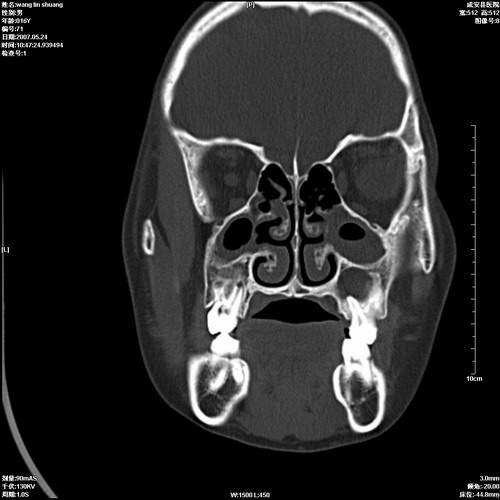

病人,男 16岁,鼻旁右肿胀,其余无不适感,ct图片

1、典型右侧根尖囊肿。

2、双侧上颌窦、筛窦、蝶窦炎

1\\左侧上颌骨含牙囊肿

2\\两上颌窦炎

右侧上颌骨含牙囊肿.双侧上颌窦炎症.

右侧上颌骨含牙囊肿.双侧上颌窦、蝶窦右侧炎症.

1、左侧上颌骨含牙囊肿。

典型的右侧上颌骨含牙囊肿,双侧上颌窦、右侧蝶窦炎症。